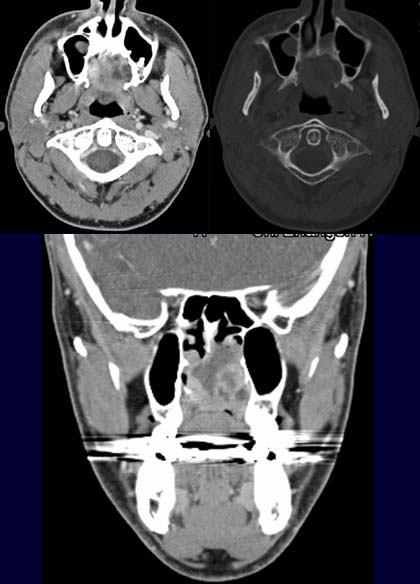

Im

axialen CT-Schnitt, nach KM-Gabe (linkes oberes Bild), kommt im Bereich des

Gaumens eine inhomogen KM-aufnehmende Raumforderung zur

Darstellung. Im Knochenfenster (rechtes oberes Bild) kommt die knöcherne

Destruktion des Gaumens zur Darstellung. Nebenbefundlich kommt

eine polypöse

Schleimhautschwellung des Sinus maxillaris rechts zur Darstellung.

Im koronaren CT-Schnitt (unteres Bild) kommt die kraniokaudale Darstellung

der Raumforderung gut

zur Darstellung, man sieht wie die Raumforderung sich zwischen Mundhöhle

und Nasenhaupthöhle ausbreitet.